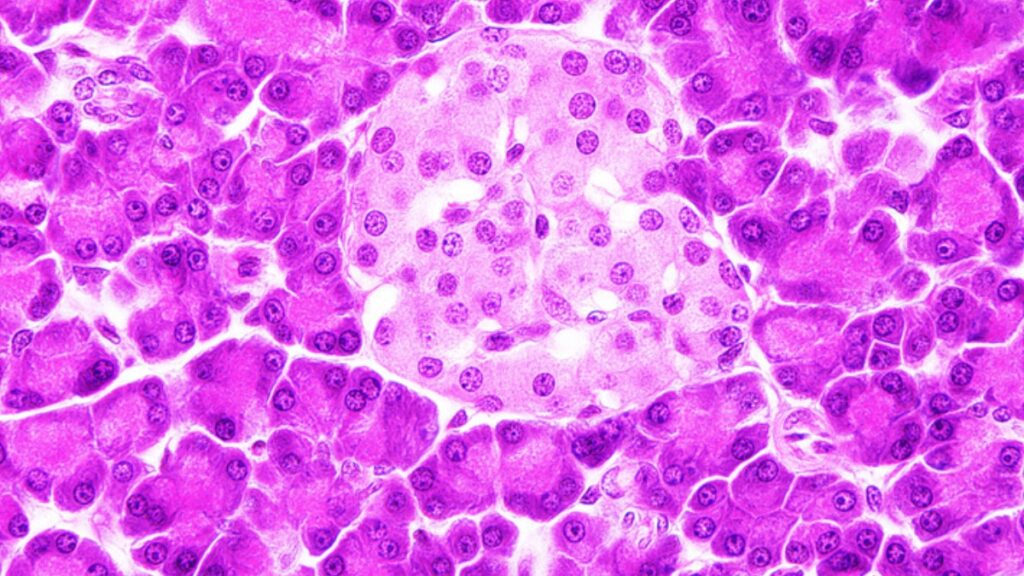

IMAGEM DE CAPA: ilhota pancreática (rosa claro) circundada por ácinos do pâncreas exócrino (rosa escuro.) FONTE: Microscopia on line, 3v, USP.